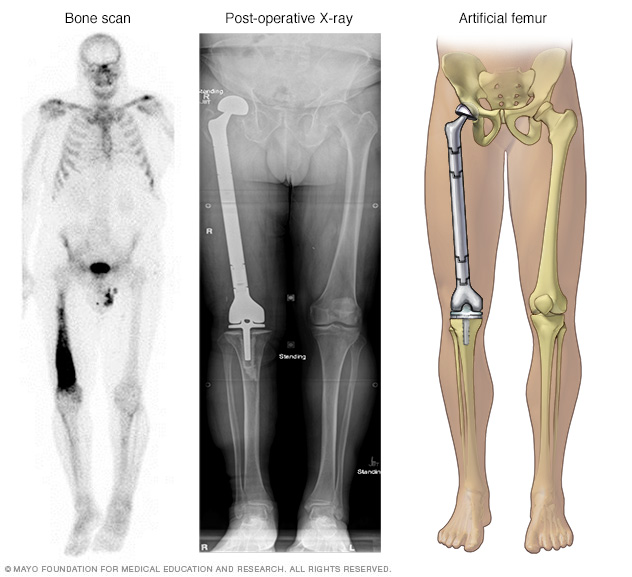

- Cutting away the cancer and some healthy tissue around it. Most chondrosarcomas require a procedure to cut away more of the bone in order to remove all of the cancer. For chondrosarcoma in an arm or a leg, it might be necessary to remove the entire limb. When possible, surgeons remove the cancer in a way that preserves the limb. For example, the surgeon might remove the affected bone and replace it or reconstruct it (limb salvage surgery).